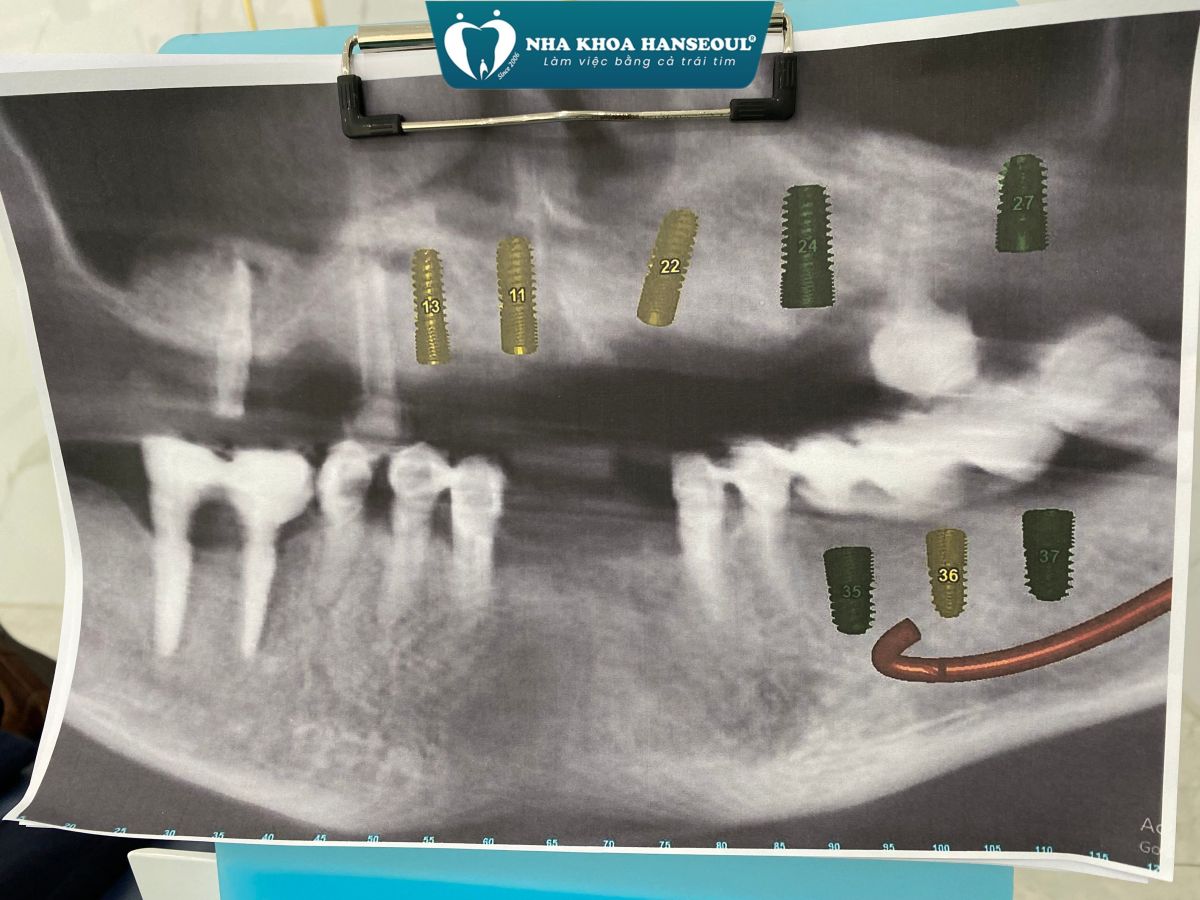

Khi tiếp nhận thăm khám, bác sĩ nhận thấy:

- Hàm trên: chỉ còn lại vài trụ Implant cũ đã được đặt cách đây hơn 10 năm, hiện nay có dấu hiệu tiêu xương quanh trụ, không còn đảm bảo chức năng nâng đỡ phục hình.

- Hàm dưới: nhiều mão sứ và cầu răng đã xuống cấp, lỏng, gãy, gây mất cân đối khớp cắn và ảnh hưởng đến khả năng ăn nhai.

- Xương hàm có dấu hiệu tiêu và mỏng, cần được đánh giá kỹ qua phim CT ConeBeam 3D để xác định có cần ghép xương, nâng xoang trước khi cắm trụ mới.

Sau khi hội chẩn, bác sĩ Cao Việt Hải đã đưa ra kế hoạch điều trị rõ ràng, khoa học và phù hợp với tình trạng của bệnh nhân:

- Hàm trên: Cấy ghép Implant toàn hàm bằng kỹ thuật All-on-5 – giải pháp phục hồi tối ưu giúp tái tạo toàn bộ hàm răng trên chỉ với 5 trụ Implant, mang lại độ vững chắc và thẩm mỹ cao.

- Hàm dưới: Đặt thêm Implant Hiossen (Mỹ) để phục hình lại các răng mất, đảm bảo khả năng chịu lực tốt, tích hợp xương nhanh và tuổi thọ lâu dài.